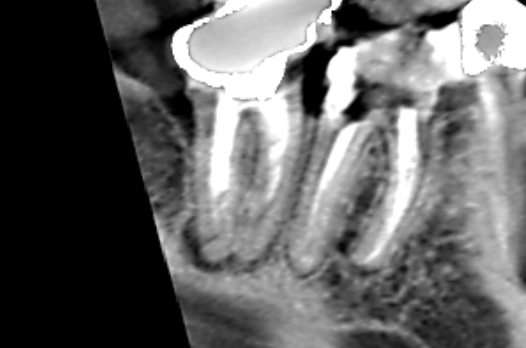

Vol.41 下顎第二小臼歯と下顎第一大臼歯の近心根の両方の根にまたがる膿がみられたケース 2025年12月03日 イスムス清掃・ 下顎第二小臼歯・ 外科的歯内療法後の再発・ 歯槽骨再生・ 精密再根管治療 下顎第二小臼歯と下顎第一大臼歯の近心根の両方の根にまたがる膿があり、口腔外科で外科的歯内療法を受けた… 続きを読む Vol.40 下顎第二大臼歯の遠心根に膿がみられたケース 2025年12月03日 CT診断・ 下顎第二大臼歯・ 歯槽骨再生・ 湾曲根管・ 精密再根管治療 患者さんは特に自覚症状をお持ちでなかったのですが、他の歯の治療でCTを撮影したところ下顎第二大臼歯の… 続きを読む Vol.39 上顎第一大臼歯の近心根に膿がみられたケース 2025年11月13日 上顎第一大臼歯・ 根尖病変・ 根管形態・ 精密再根管治療・ 近心頬側根 上顎第一大臼歯の近心根に膿がみられました。実は、Vol.37、Vol.38、Vol.39は同じ患者さ… 続きを読む Vol.33 歯茎の腫れの原因は隣の歯にあったケース 2025年10月21日 原因歯の特定・ 歯根破折・ 歯槽骨再生・ 歯茎の腫れ・ 精密再根管治療 根管治療を受けているが歯茎の腫れが治らないということで当医院に来院された患者さんです。来院時には… 続きを読む